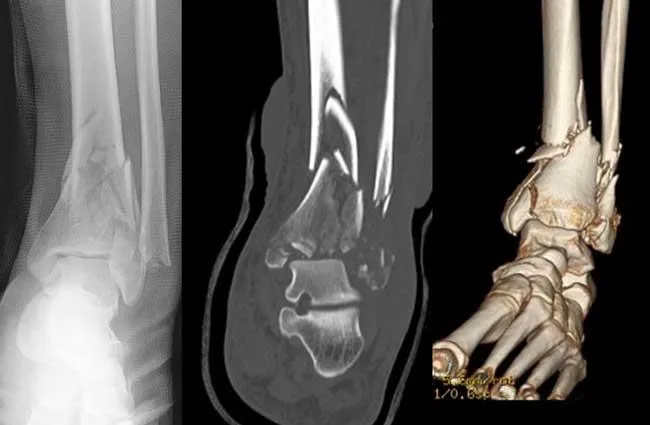

3. Beeldvorming:

Er worden röntgenfoto’s van de enkel gemaakt. Hierop is de pilonfractuur meestal goed te zien, inclusief eventuele versplintering in het gewricht. Vaak laat de arts een CT-scan maken om de details van de botbreuk en gewrichtsschade in beeld te brengen. Dit is belangrijk om de operatieve behandeling goed te kunnen plannen.